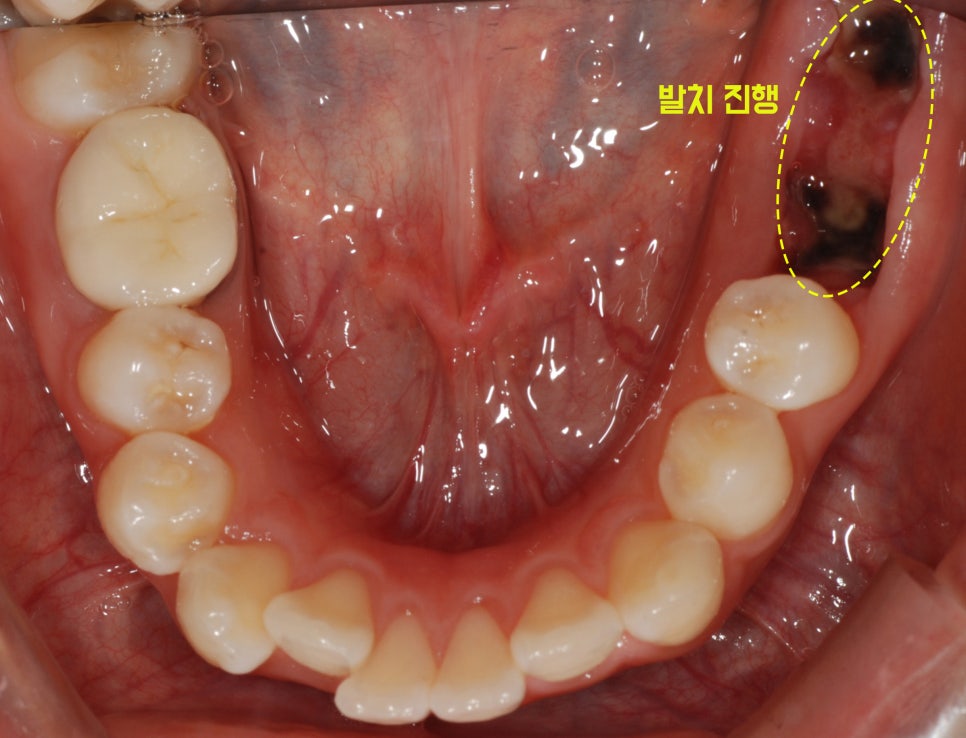

충치가 잘 생기는 체질에 심한 충치로 인해 왼쪽 아래 어금니 2개를 방문 직전 발치하셨던

20대 여성 환.자분께서 내원하셨습니다:)

내원 당시 촬영하였던 구강 내 사진을 한 번 확인해 볼까요?

환.자분의 구강 내 사진을 확인해 보면 한눈에 봐도 치열이 고르지 않고 입이 돌출되어 보이는 양상을

보이고 있는 모습이 눈에 띄었습니다.

앞니들은 이가 배열될 공간이 부족하여 치아들이 고르게 맹출하지 못하였으며 이를 “총생”이라고 부릅니다.

이런 경우에는 하악이 열성장을 보이는 골격성 2급 부정교합으로 진단합니다.

또한 하악골의 우측 변위를 동반한 안면 비대칭이 있었습니다.